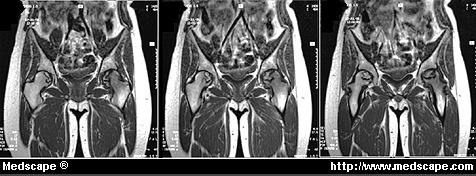

Figure 4. MRI showing juxta-articular avascular osteonecrosis of the hip. Reprinted with permission from the Virtual Hospital. La MRI mostra osteonecrosi avascolare vicino all’articolazione dell’anca.

La risonanza magnetica (Magnetic resonance imaging – MRI) (Fig.4) riesce ad individuare precocemente le lesioni, ma costosa generalmente non rientra tra gli esami di screening per una ampia popolazione. Fu usata nel 1981 dal Decompression Sickness Registry, il quale ha rilevato che la percentuale di necrosi, sia articolare che ossea, aumenta in un campione di subacquei con l’età e con l’esperienza.

Da ciò si può supporre che esaminare dei subacquei “profondisti”con MRI può aiutare a diagnosticare lesioni articolari e a prevenirne il collasso. ( 9)